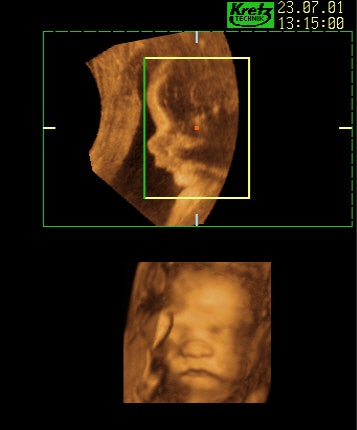

![]() |

| Figure 3, a comparison between a 2-D and 3-D representation of a baby’s face. Image courtesy of Dr. Stefano Ciatti. Upper image: A traditional 2-D ultrasound line profile of the baby’s face (perhaps the most easily recognized line representation of the baby that the parents-to-be can understand). Lower image: A photographic-style representation of the same baby’s face by 3-D ultrasound that parents-to-be can readily understand and appreciate. |

Women in our study underwent grayscale traditional ultrasound imaging followed by color 3-D ultrasound imaging. Two-dimensional traditional ultrasound pictures demonstrate line representations of the developing baby (for example, the outline profile of the baby’s face), whereas 3-D ultrasound images produce a more realistic representation of the fetus (for example, a photographic-style image of the whole face including eyes, lips, nose, cheeks, etc.).